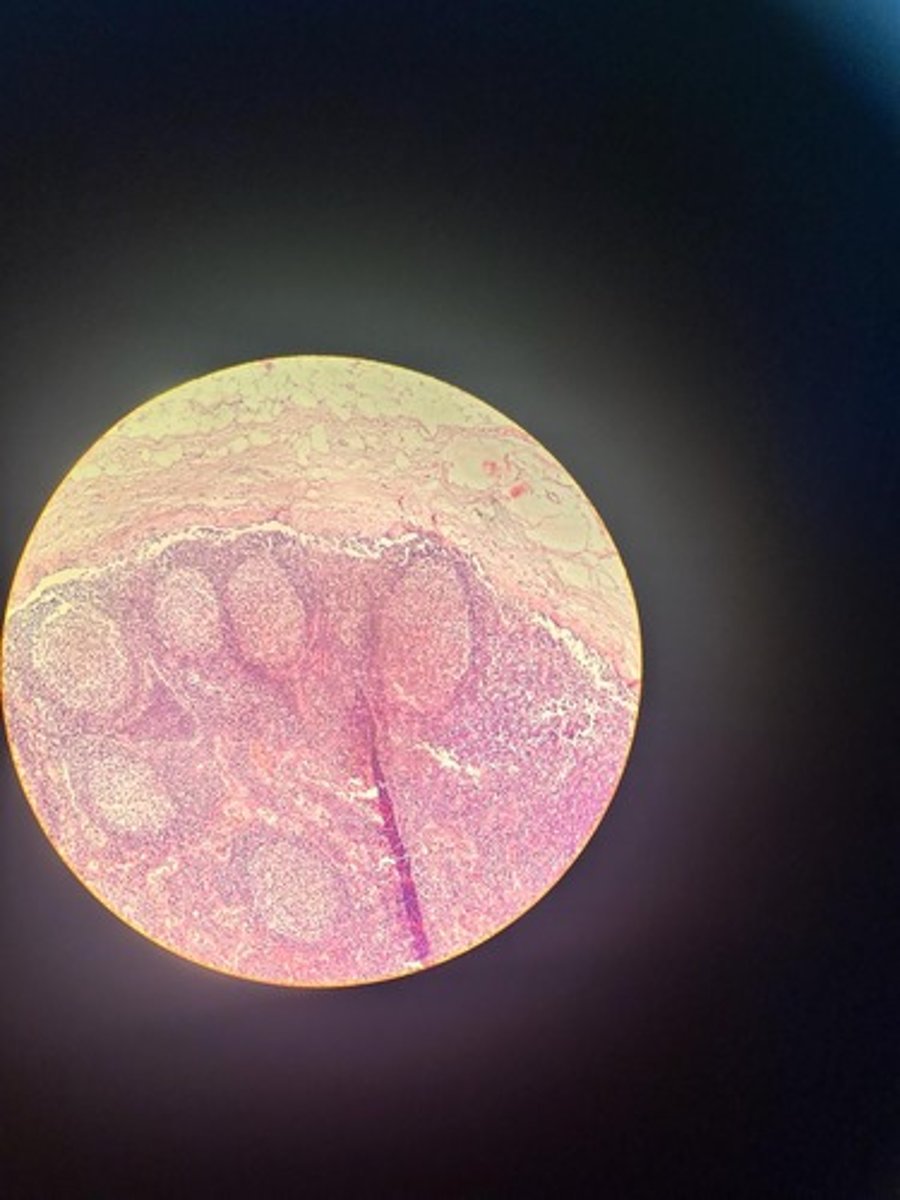

Lymph node HE

Lymph node HE

Lymph node HE

lymph node HE

Lymph node HE

Lymph nodes HE